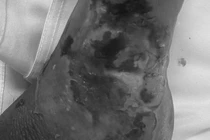

Tuy nhiên, chỉ sau một tháng, tình trạng chuyển biến xấu, vùng cẳng chân trái sưng tấy đỏ, viêm tấy lan từ bàn chân lên gần hết cẳng chân, xuất hiện nhiều bóng nước và phù nề mô mềm. Gia đình vội đưa bà vào Trung tâm Y tế trong tình trạng nhiễm trùng nặng.

mun-nho.jpg

Ca phẫu thuật cho bệnh nhân - Ảnh BVCC

Tại đây, bác sĩ chẩn đoán bà H. bị nhiễm trùng lan tỏa cẳng chân trái và được tiến hành phẫu thuật xử trí vết thương, làm sạch ổ nhiễm kết hợp điều trị kháng sinh tích cực.